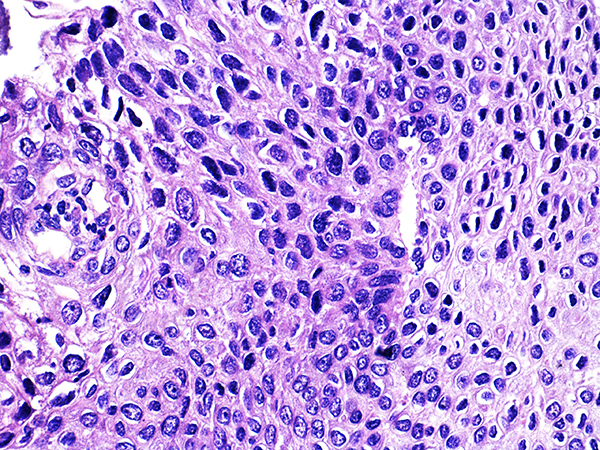

![]() Case 2

Soft Bx CIN 2 10x - Low Power |

Soft Bx CIN 2

40x - High Power